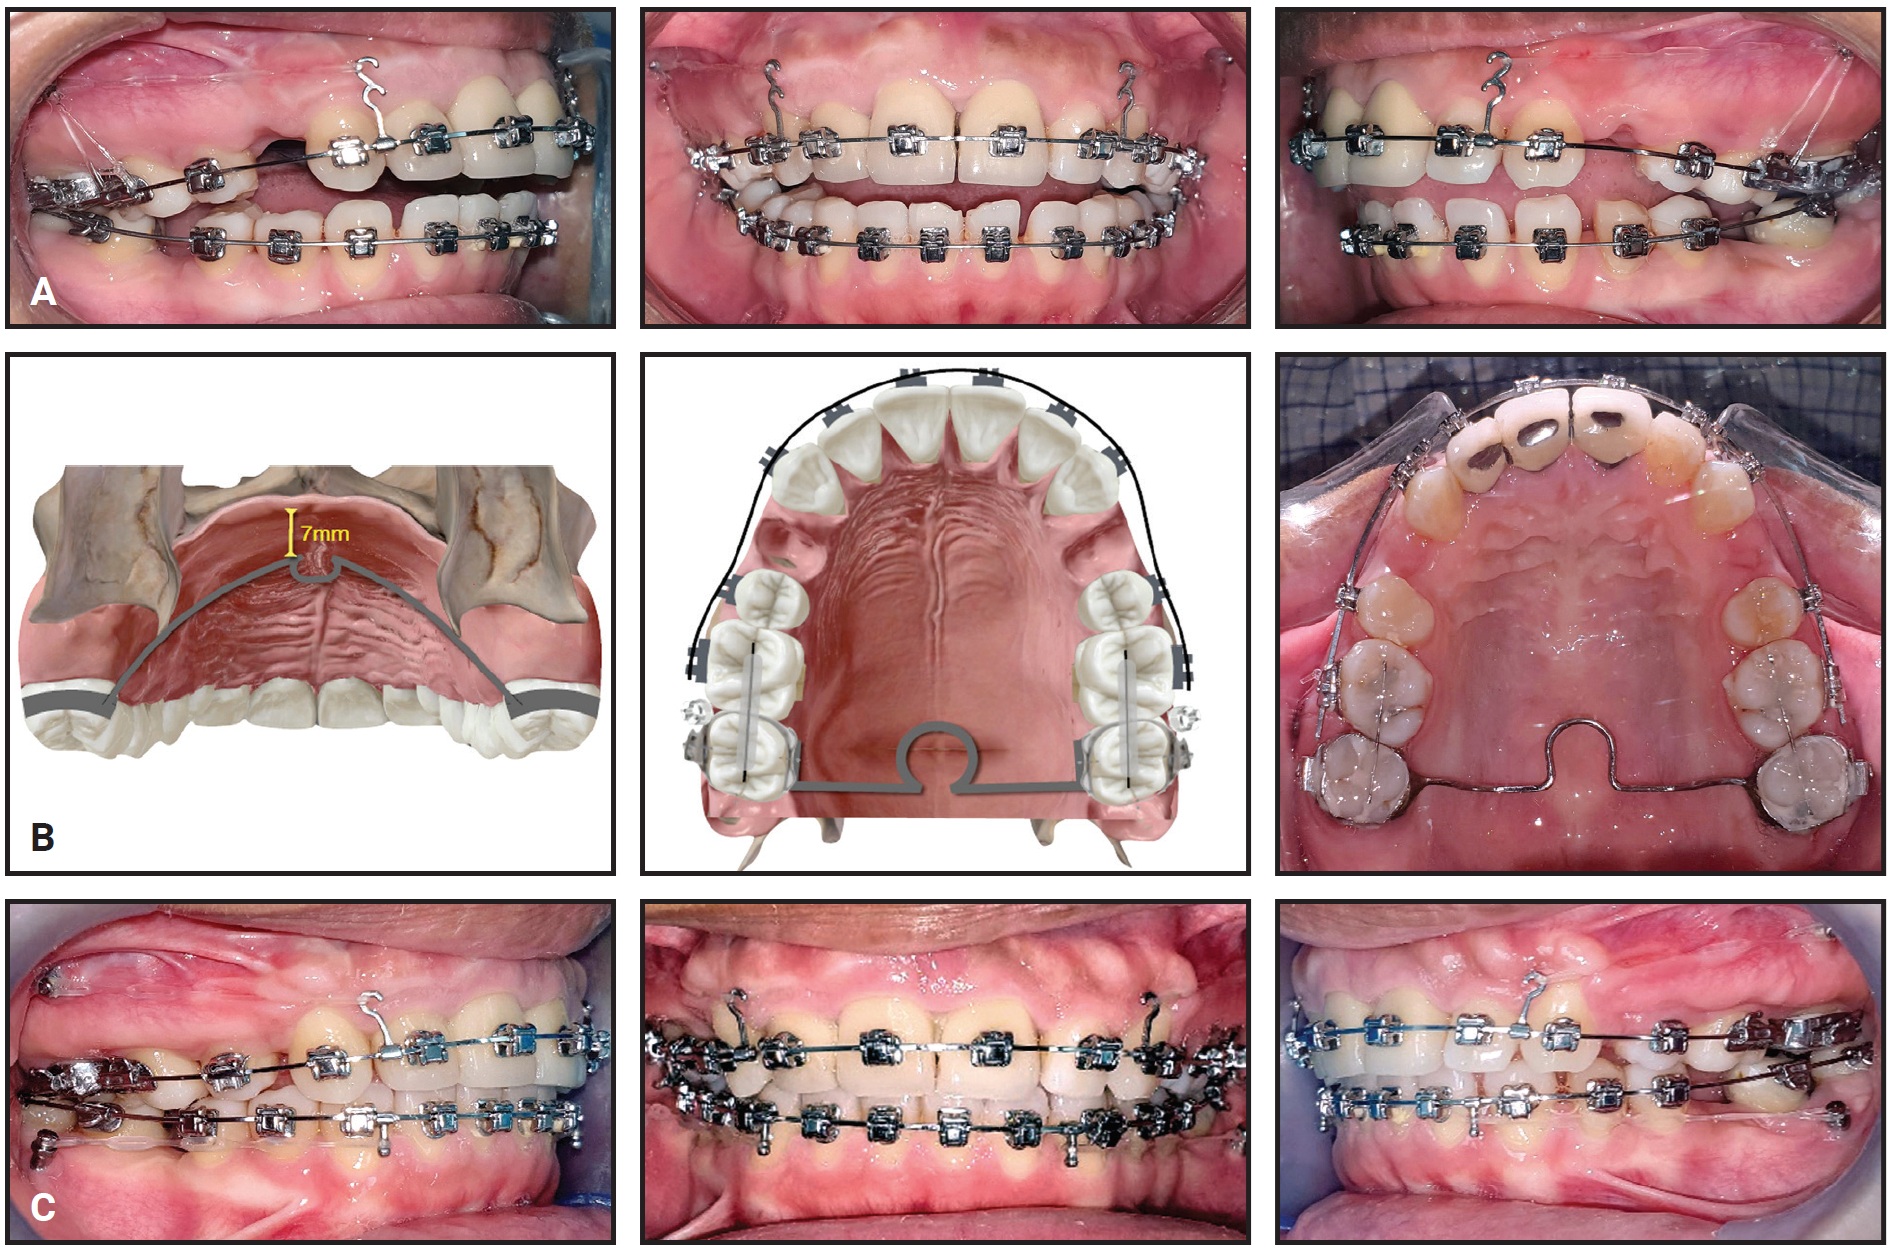

Primo** .022" labial brackets were bonded indirectly, and .014" nickel titanium archwires were inserted in both arches (Fig. 7). An open-coil spring was placed between the upper right lateral incisor and first premolar to provide space for eruption of the ectopic canine and to help center the upper dental midline.

Fig. 7 Primo** .022" labial brackets bonded and .014" nickel titanium archwires inserted in both arches; open-coil spring placed between upper right lateral incisor and first premolar to provide space for canine eruption and to center upper dental midline.

Two months later, when enough space had been created for the upper right canine, its eruption was initiated by tying an elastic module to its mesial bracket wings and to the archwire27 (Fig. 8).

After four months of canine alignment, an .019" × .025" nickel titanium archwire was inserted in the upper arch to continue leveling (Fig. 9). An .019" × .025" stainless steel archwire was inserted in the lower arch, with elastomeric chain added to close existing spaces and to prevent unwanted spaces from opening between the lower canines and lateral incisors. For sagittal and anterior vertical correction, the patient was asked to wear ³⁄16", 6oz Class III elastics*** 22 hours per day in a triangular configuration from hooks on the upper and lower canines to hooks on the upper first molars.

Fig. 8 Two months later, with sufficient space gained for upper right canine, eruption initiated with elastic module tied to mesial bracket wings and archwire.

Fig. 9 After four months of canine alignment, upper .019" × .025" nickel titanium and lower .019" × .025" stainless steel archwires inserted, with elastomeric chain added in lower arch for space closure.

Two months later, the brackets on the upper right central incisor and lower right first premolar were repositioned for finishing and detailing, and Class III elastics were applied asymmetrically to center the upper and lower dental midlines (Fig. 10).

Fig. 10 Two months later, brackets repositioned on upper right central incisor and lower right first premolar for finishing and detailing.